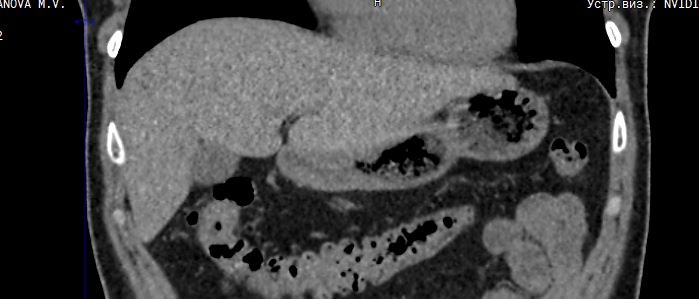

Мультиспиральная компьютерная томография желчного пузыря применяется для оценки состояния стенок желчного пузыря, изучения содержимого его полости, выявления воспалительных изменений, конкрементов и опухолевых новообразований.

В клинике «Доступная медицина» исследование проводится на новейшем 128-срезовом томографе TOSHIBA AQUILION CXL, который позволяет проводить исследование за короткий промежуток времени при сниженной лучевой нагрузке. Посредством инновационных компьютерных программ томограф преобразует полученные данные в 3D-изображения желчного пузыря и желчевыводящих протоков. Это помогает диагностировать заболевания гепатобилиарной системы особенно при нетипичной клинической картине, когда при помощи других методов обследования (УЗИ, МРТ) не удается выявить причину нарушения оттока желчи из желчного пузыря.

МСКТ желчного пузыря в большинстве случаев проводится с применением контрастирования. Пациенту внутривенно вводится рентгеноконтрастное вещество на основе йода. Препарат с током крови попадает в исследуемую область и усиливает контрастность патологических участков, что делает их видимыми на фоне здоровых тканей. При подозрениях на онкологический процесс метод компьютерной томографии с контрастированием помогает обнаружить патологию на раннем этапе развития и провести своевременное лечение.

Что покажет КТ желчного пузыря

- камни желчного пузыря и его протоков;

- холангит и холецистит;

- абсцессы;

- нарушения кровоснабжения, травмы, кровоизлияния;

- воспалительные процессы в желчном пузыре и поджелудочной железе.